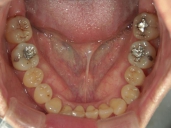

矯正歯科 治療前 上顎

矯正歯科 治療前 下顎